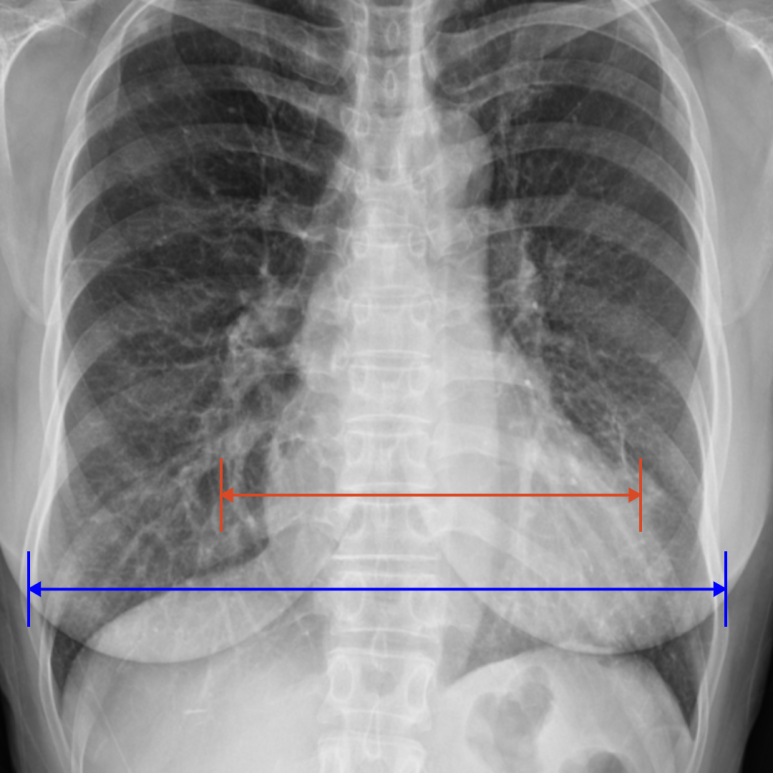

1. 흉부 X‑ray

• X‑ray: 심비대 의심 X‑ray: 심비대 의심